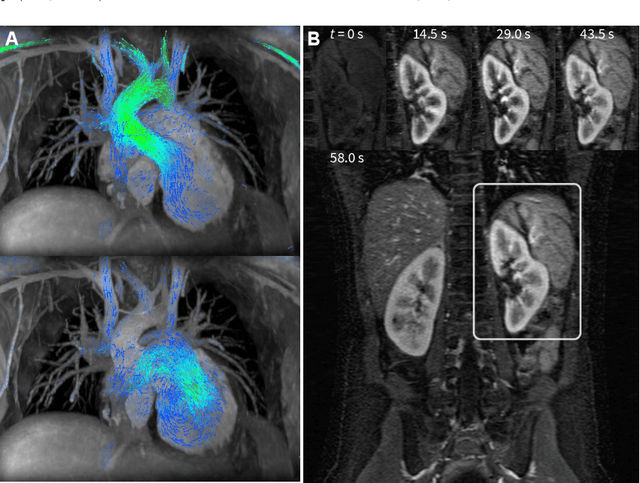

Abstract:Deep learning-based image reconstruction methods have achieved promising results across multiple MRI applications. However, most approaches require large-scale fully-sampled ground truth data for supervised training. Acquiring fully-sampled data is often either difficult or impossible, particularly for dynamic contrast enhancement (DCE), 3D cardiac cine, and 4D flow. We present a deep learning framework for MRI reconstruction without any fully-sampled data using generative adversarial networks. We test the proposed method in two scenarios: retrospectively undersampled fast spin echo knee exams and prospectively undersampled abdominal DCE. The method recovers more anatomical structure compared to conventional methods.